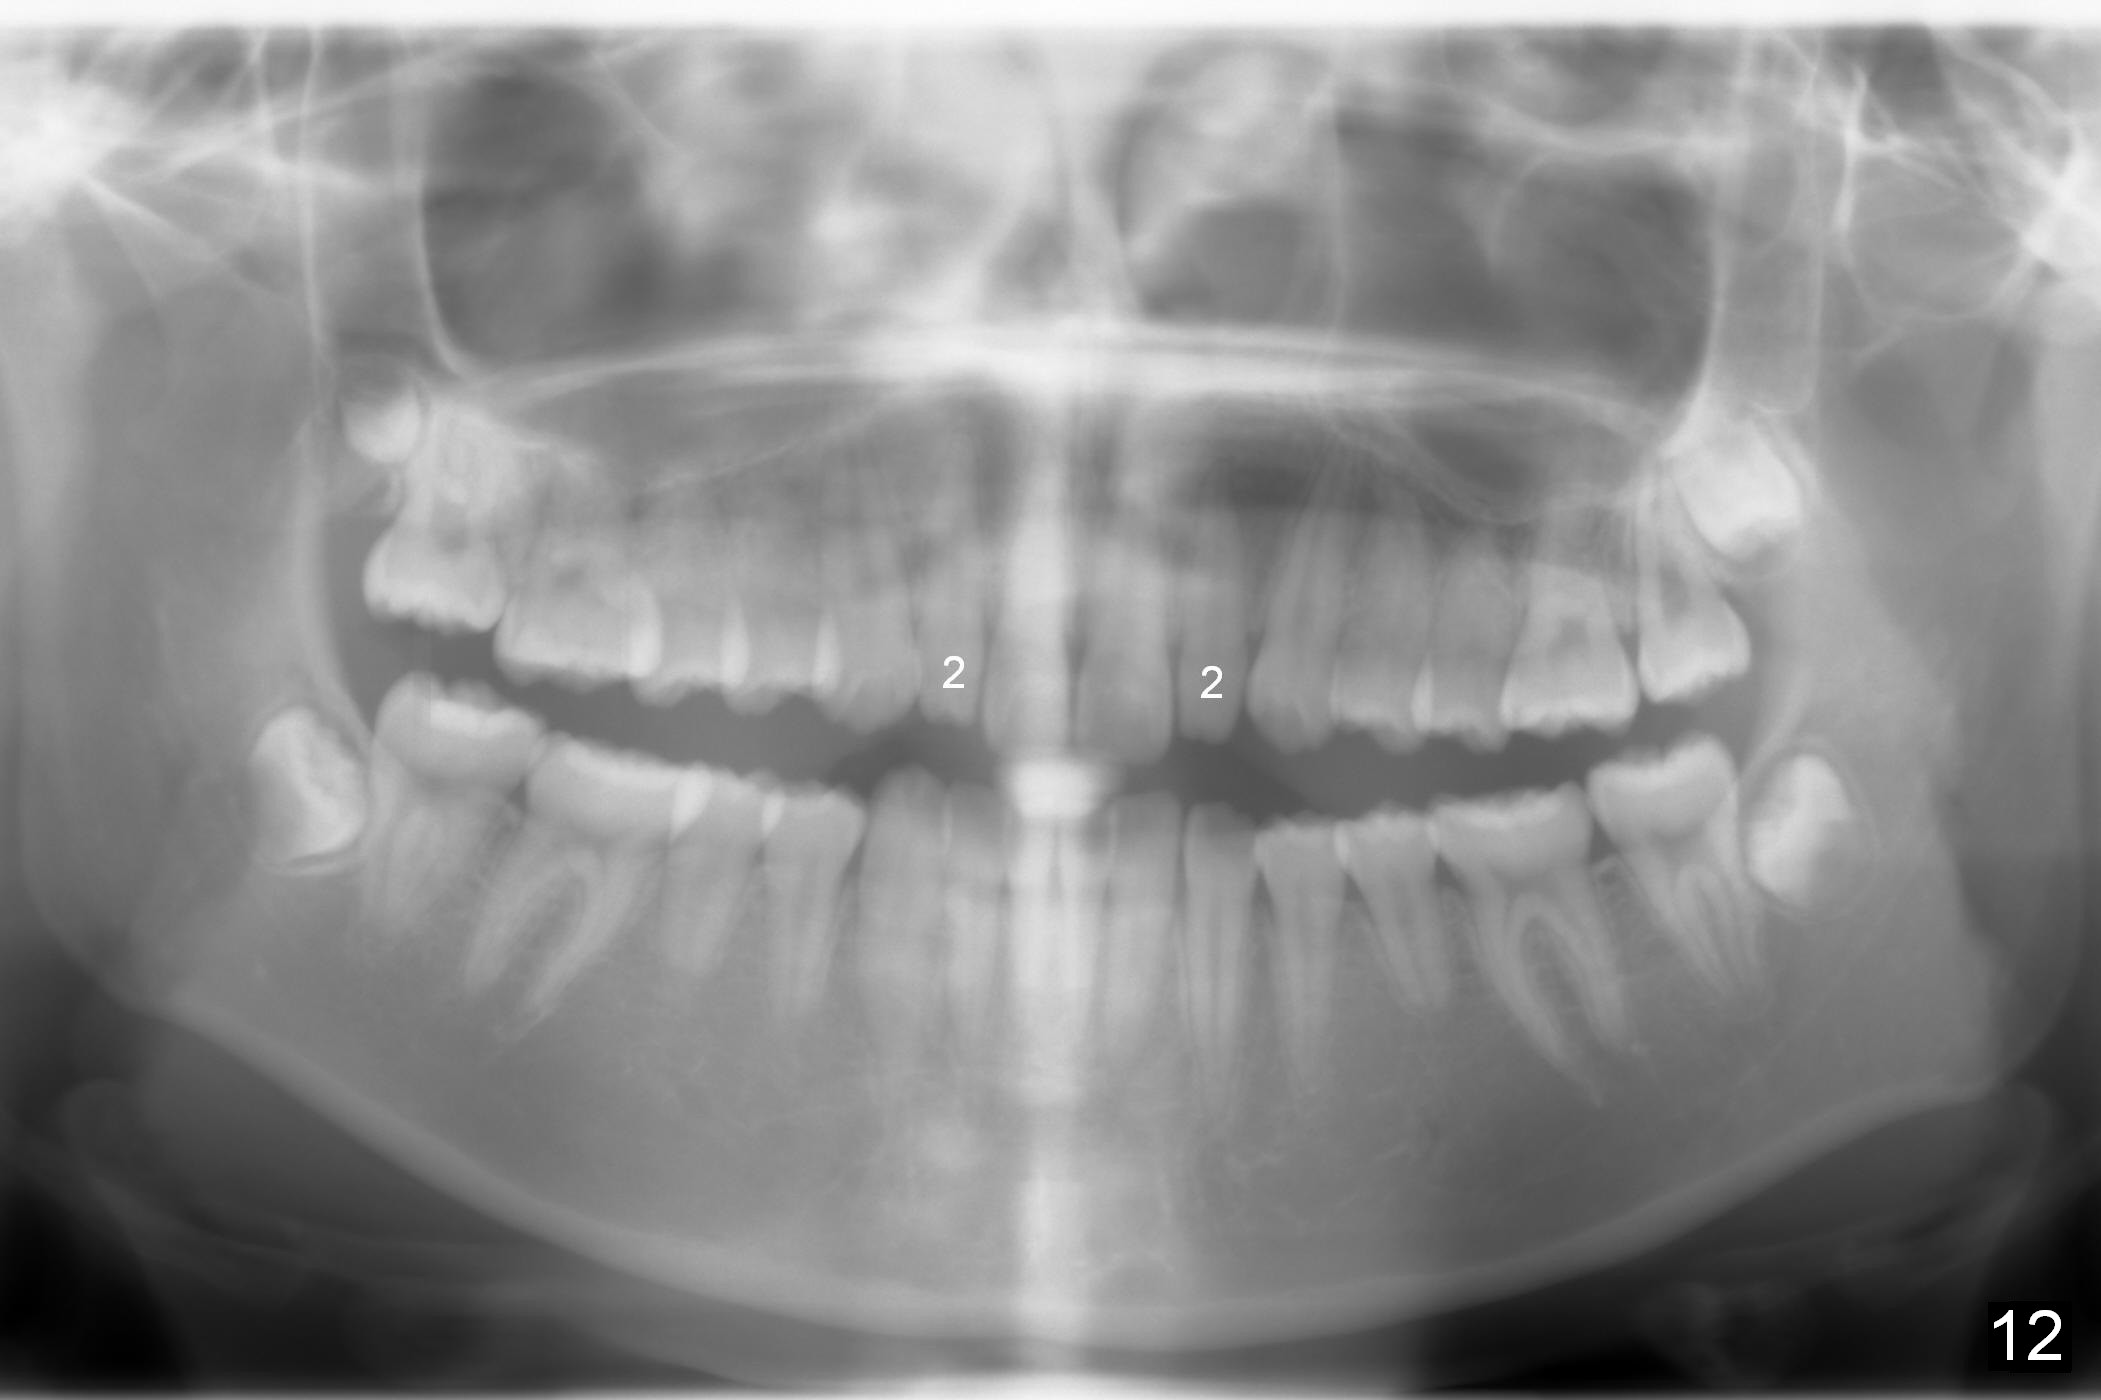

A 13-year-old girl denies mouth breath/nasal obstruction in spite of pointed narrow arches (Fig.10,11). When she is relaxed, the lips remain unclosed (Fig.1). There is lip strain when they try to close (Fig.2). When the patient is smiling, the upper central incisors have extra exposure (Fig.3). Differential bracket placement between U1 and U3 (4 vs. 5 mm from the incisal edge) should be able to correct the exposure. Profile views show the mild lip protrusion (Fig.4,5). Class II elastic retraction when arch wires reach 18 ss may be able to move the lower arch forward (Fig.6 arrow) and/or move the upper one backward (take care of Class II malocclusion (Fig.8,10) and lip profile).

Microdontia at U2s contributes to Class II malposition of U3s (Fig.7,9). No brackets are placed in U2s initially so that open coil springs can be placed between U2 and 3 to increase space. Composite veneers are to be fabricated near the end of orthodontic treatment, whereas porcelain veneers are going to be placed when she grows beyond puberty. Constantly encourage the patient for better oral hygiene before, during and after orthodontic treatment (Fig.8,9). Without extraction, the facial profile remains convex postop.